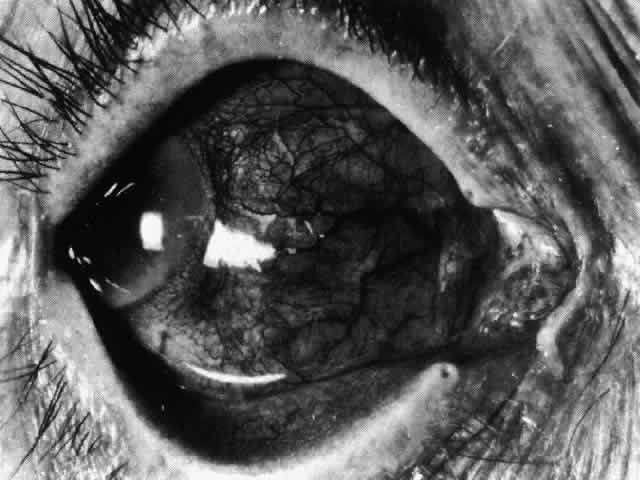

With the increasing use of anterior segment fluorescein angiography in the early detection of severe necrotizing disease of the sclera, it is necessary to have an understanding of the normal anatomy of the vasculature of the anterior segment of the eye.3–5 The blood supply to this region is enormous, being derived from the anterior ciliary arteries, but with extensive collateral arterial anastomoses to the posterior ciliary arteries at the root of the iris (Fig. 1). The anterior system is readily visible with the slit lamp and by anterior segment fluorescein angiography, especially if the eye is inflamed, and its recognition is of vital importance in the differentiation of episcleral and scleral conditions. The separation and displacement of these vascular layers give the most important clinical clues to the site and, hence, the severity of the inflammation. On slit lamp examination, three layers of vessels are readily visible. The conjunctival plexus, which is the most superficial layer of vessels, can be moved over the underlying structures. The superficial episcleral capillary plexus (Fig. 2) is a radially arranged series of vessels lying within the parietal layer of Tenon's capsule. The vessels in this layer anastomose at the limbus with the conjunctival vessels, with other members of the same plexus, and with the deep plexus. The deep episcleral capillary network (see Fig. 2) is closely applied to the sclera in the visceral layer of Tenon's capsule. The vessels anastomose freely with each other, forming a syncytium. The large vessels to and from the intrascleral plexus traverse the episclera near the insertions of the muscles. The conjunctival and superficial episcleral vessels can be blanched with 1:1000 epinephrine or 10% phenylephrine, but the deep vessels are affected slightly. This is of considerable assistance when attempting to differentiate deep and superficial inflammation.

Fig. 2. The normal relationships of the capillary networks that can be seen with the slit lamp are a conjunctival (easily mobile) network, a superficial episcleral network in the parietal layer of Tenon's capsule, and a deep episcleral plexus closely applied to the sclera. These relationships are much more obvious in inflamed eyes (see Figs. 13, 14, and 30). (Watson PG, Hayreh S, Awdry P: Episcleritis and scleritis. Br J Ophthalmol 52(3):278– 279, 1968)